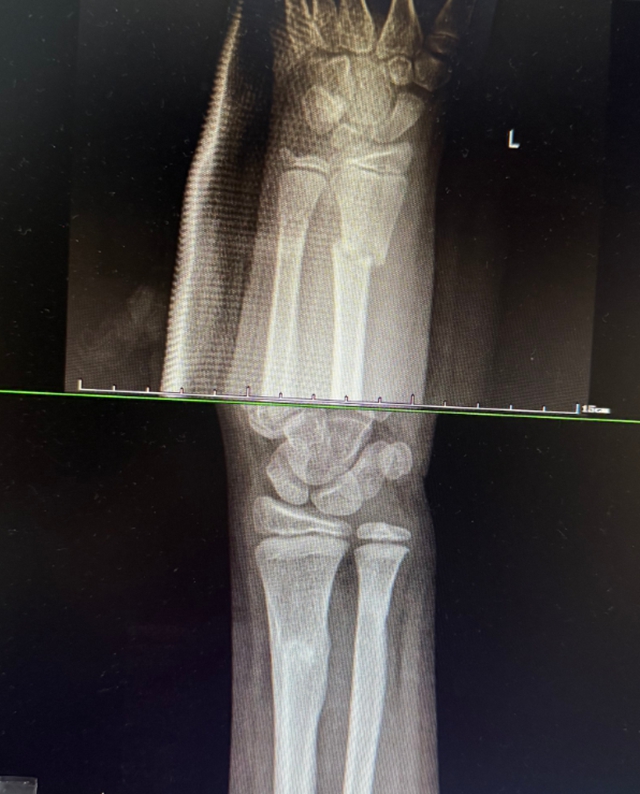

西安9岁女孩小璐(化名)玩耍时意外摔倒,导致左手前臂扭曲。紧急送医后,X光片显示其尺桡骨双骨折,断端已移位。父母带她辗转当地多家医院,均建议手术复位。

次日,一家人从西安来到医院正骨病房。此时付至江主治中医师刚结束治疗,便立刻接过病历和片子。细细比对后,他轻触小璐前臂检查,动作轻柔:“孩子骨骼柔韧,尺桡骨双骨折,首选中医正骨保守治疗……”这句话让小璐妈妈喜极而泣。

5分钟完成复位,小璐迟疑地抬起手臂,瞬间笑了:“妈妈,没那么疼了!”

康复归来,三月余重绽舞姿